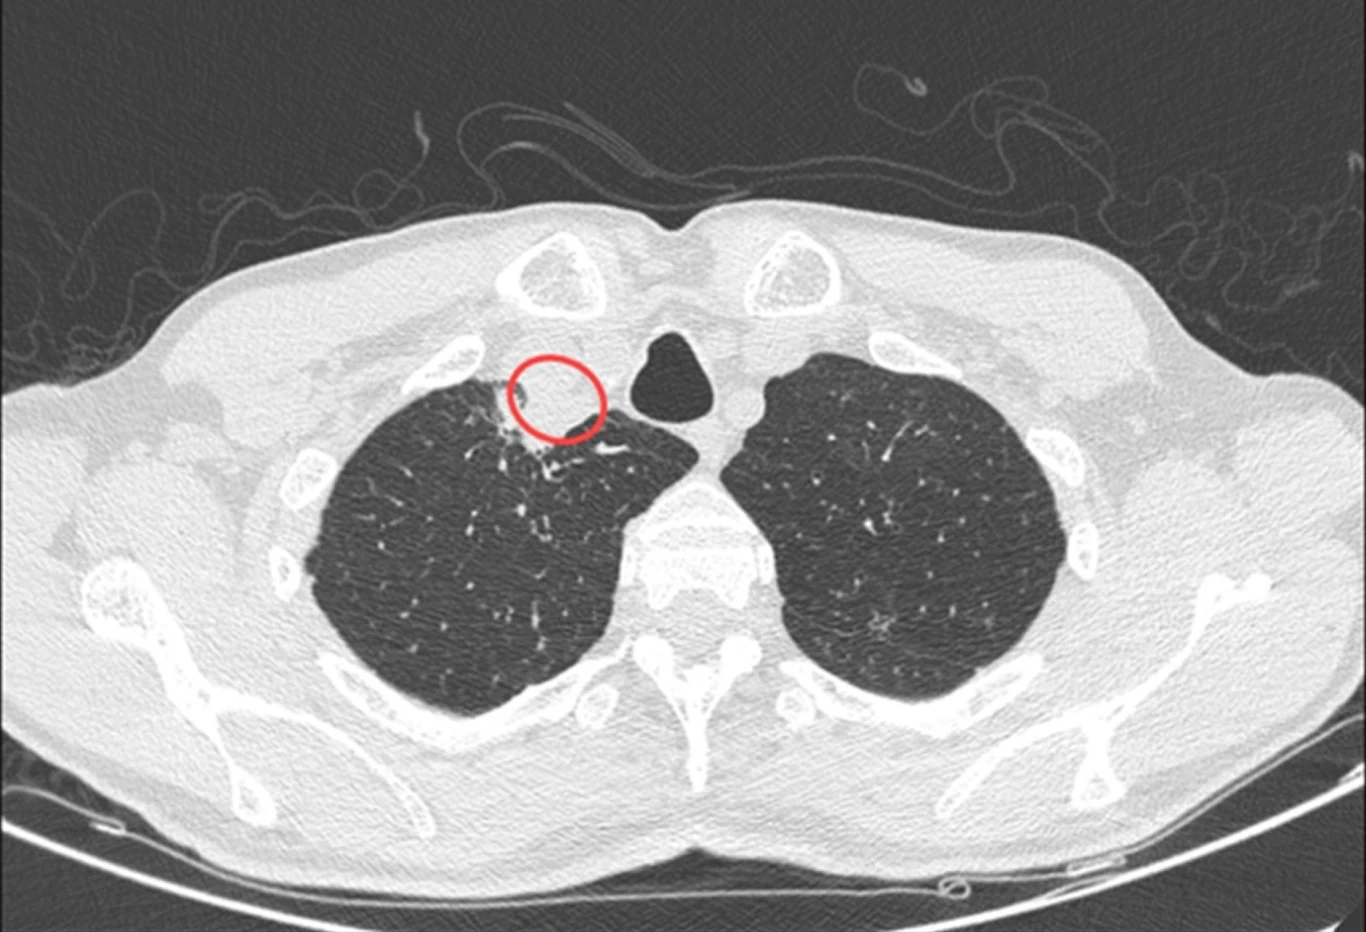

Tomografia wykazała u mężczyzny ropień w okolicach tchawicy. Pobraną z niego ropę przekazano do dalszych badań. Po wielu nieudanych próbach materiał zidentyfikowano wreszcie jako pochodzący od chrząstkoskórnika purpurowego.